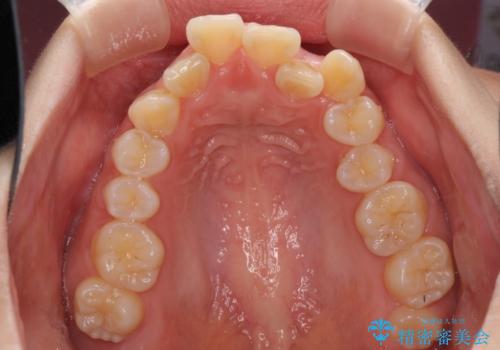

- 上下前歯の叢生と八重歯を気にして来院された患者様です。

前歯部叢生のスペースを獲得するため、上下顎左右小臼歯各1歯を抜歯することとしました。